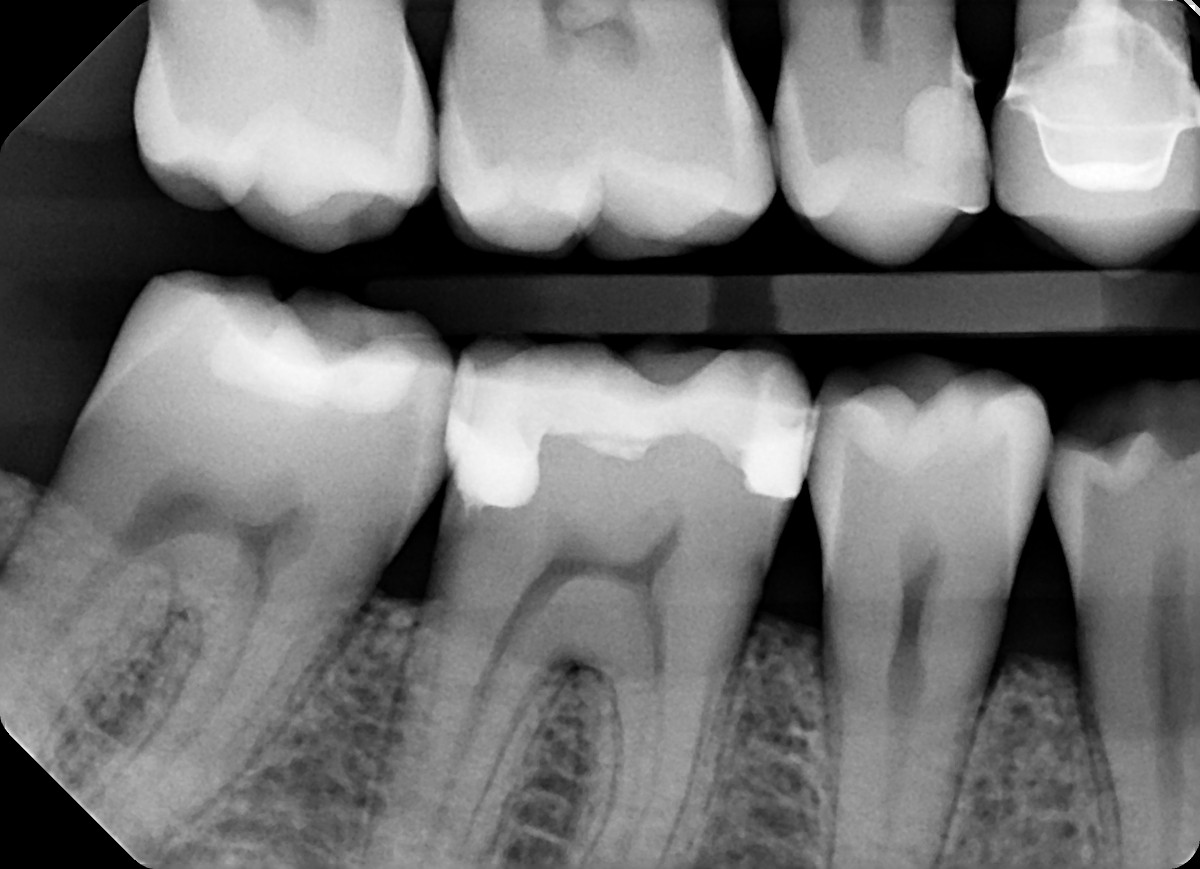

1.  In the X ray bellow for which jaw periodontal bone loss is evident?